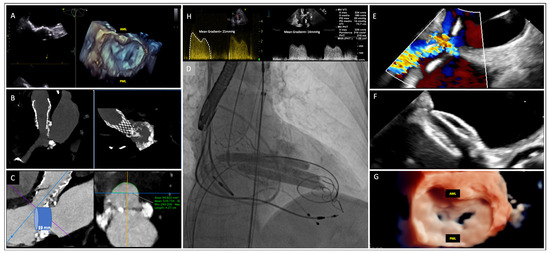

1.1. A Case of Transcatheter Mitral Valve Lithotripsy without Percutaneous Balloon Valvuloplasty for Palliative Treatment of an Extremely Calcified Degenerative Mitral Valve Stenosis

2. Diagnosis

2.5. Evaluation of MAC

3.2.4. Transcatheter Mitral Valve Replacement

- Left ventricular outflow tract (LVOT) obstruction due to the permanent displacement of the anterior mitral leaflet towards the interventricular septum, creating a narrow and elongated neo-LVOT. This obstruction remains fixed. The obstruction becomes dynamic when neo-LVOT induces Bernoulli forces, pulling the mitral leaflet against the interventricular septum during systole. The strongest CT-predictors of LVOT obstruction are the LVOT area and the predicted neo-LVOT area (after valve implantation). By simulating the placement of a virtual valve in the mitral annulus, pre-planning CT enables the prediction of the neo-LVOT area across different systolic phases of the cardiac cycle. Yoon et al. showed that an estimated neo-LVOT area of ≤1.7 cm2 predicted LVOT obstruction with a sensitivity and specificity of 96.2% and 92.3%, respectively. In addition, aorto-mitral angulation close to 90°, a small left ventricular cavity, and basal hypertrophy (<15 mm) were also found to be risk factors for post-TMVR LVOT obstruction [54]. In these cases, pre-emptive techniques to avoid LVOT obstruction, such as LAMPOON (laceration of the anterior mitral leaflet to prevent outflow obstruction) or ASA (alcohol septal ablation) technique should be performed. The LAMPOON technique consists of intentional laceration of the anterior MV leaflet using catheters placed in the left atrium and LV to puncture the anterior leaflet and lacerate it with electrocautery. Early experience with this technique on 30 patients achieved midline laceration of the anterior leaflet in 100% of patients and a 30-day survival rate of 93%. This technique is being studied in a prospective single-arm trial [55].